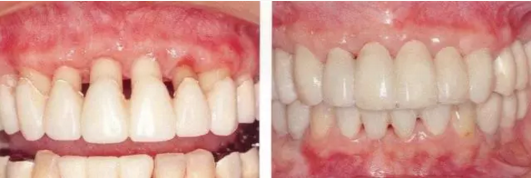

▲圖16-1~4 56歲,女性?;加腥谘乐苎浊蚁骂M磨牙區(qū)缺失,可以看到上頜前牙區(qū)有前突的現(xiàn)象。左上1和右上1無法保留。

▲圖16-5,6

1111.png

▲圖16-7

▲圖16-5~7 將左上1和右上1拔除,下頜磨牙區(qū)植入種植體,全口進(jìn)行牙周外科處理后,佩戴臨時(shí)修復(fù)體。圖16-7為佩戴臨時(shí)修復(fù)體后的狀態(tài)。由于左上2,3和右上2,3仍然前突,所以覆蓋較深。